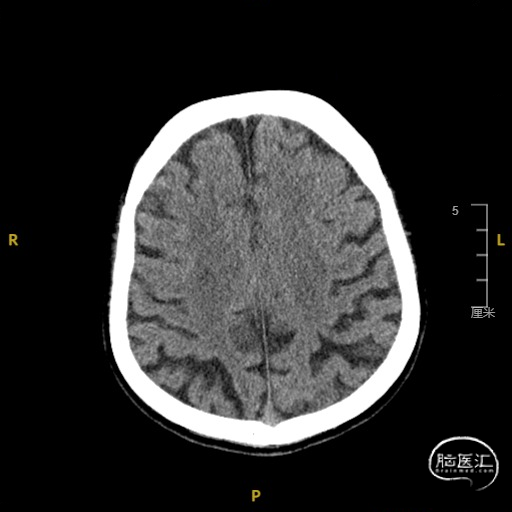

➢ 门诊头CT检查

现病史:患者于入院前3天无明显诱因出现言语不利,表现为社体笨拙,吐字不清晰,症状呈持续性,无头晕、视物旋转,无耳鸣、听力减退,无头痛、发热、恶心、呕吐,无视物不清、视物成双,无饮水呛咳、吞咽困难,无肢体活动障碍,无肢体抽搐、口吐白沫,无意识障碍及大小便失禁,就诊于我院门诊,查头CT示脑内散在缺血灶,完善颈部血管超声示双侧颈动脉内中膜增厚伴多发斑块形成,右侧颈内动脉狭窄(70-99%),右侧锁骨下动脉起始处斑块形成。TCD提示右侧大脑半球低搏动改变——考虑右侧颈内动脉颅外段病变,右侧颈内-外侧支开放,右侧大脑后动脉流速代偿性增快,左侧椎动脉狭窄(轻度)。为进一步诊治收住入院。